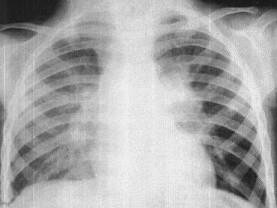

问题 女,3岁,低热、咳嗽2月余,结合胸片,最可能的诊断为?(?)

选项 A.原发综合征 B.肺门淋巴结核 C.淋巴瘤 D.支原体肺炎 E.间质性肺炎

答案 B